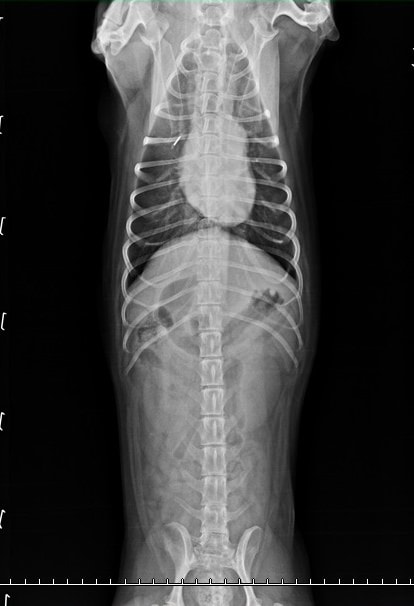

3.X光片

左邊膝蓋是鬆的,但走路看起來很好

沒有跑一跑突然掰咖,舉例來說紅貴賓容跑一跑跛腳,膝蓋會甩一下

膝關節異位這類的情況,但如果不影響日常生活就不需要手術的

左腳的膝關節有點偏移

tila是臘腸犬,可以補充關節軟骨保護劑,當作保養

有稍微擠迫一點點,但基本神經學檢查反應~腳腳的肌肉都非常好

髖關節的部分和以前沒差多少,以100分來說算85分

以臘腸品種這年紀來說算漂亮的,即早保養最好、神經傳導目前看也都好

髖關節右腳比左腳漂亮一點點 ((很愛用漂亮形容

骨骨頭左邊沒有那麼圓潤、股骨頸沒有過度的增粗

胸腰椎,每個椎體間隔都還漂亮、不會過度狹窄

胸腔、腹腔、心肺都很乾淨!漂亮!

血管很明顯

胸腔也都乾淨、無擴張,心臟大小跟以前差不多

心臟看起來很大,但臘腸狗的比例算是標準的

不用進階心臟照超音波